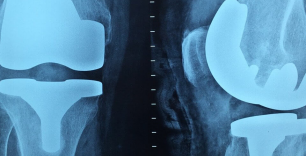

Рентген – упрощенное название неинвазивных диагностических методов, официально называемых рентгенография, рентгенологическое исследование. За счет использования рентгеновских лучей, которые проходят через тело человека, медики могут получить картину внутренних тканей и органов, определить имеющиеся патологии. В зависимости от назначений диагноста рентгенологическое исследование может проводиться в различных формах – обзорное, флюорография, ангиография, урография и так далее. Результаты исследований позволяют выявлять патологии костей, суставов, полых органов, отложения солей, скопления газов и жидкостей.